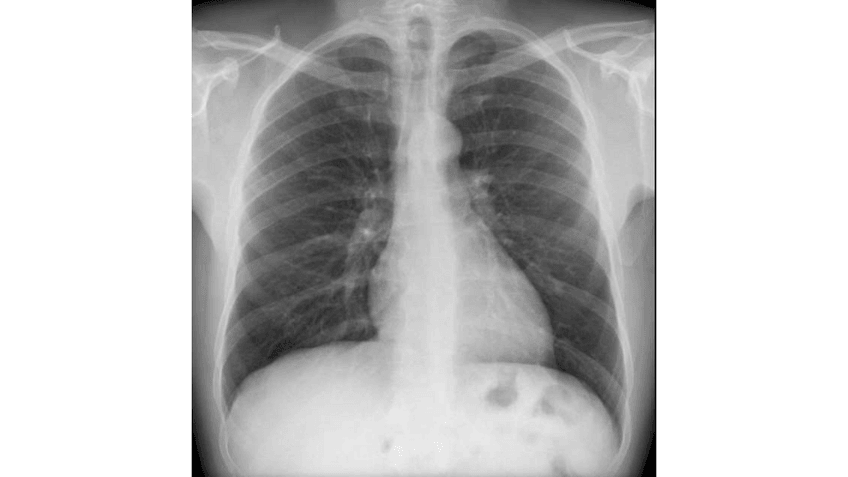

RADIOGRAFIA-DE-TORAX.pdf